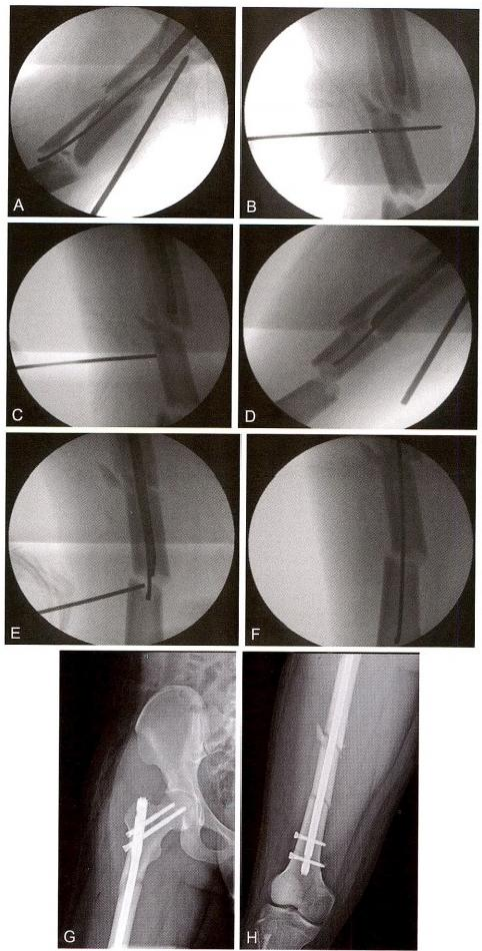

在复位手指引导下插入导针(图12-5A) 。 在复位手指配合下,透视 确定需要推顶的部位(图12-5B) 。 顶棒技术:经皮插入克氏针,推顶移 位骨块(图12-5C), 并将导针插入中间骨块髓腔(图12-5D)。 采用同样 方法,用克氏针推顶远端骨块,并插入导针(图12-5E 、F)。

图12-5 插入导针及推顶骨块。 A. 插入导针;B. 透视确认需要推顶的位置;C. 推 顶复位骨块;D. 将导针插入中间骨块;E. 撬拨复位远端骨块;F. 导针进入远端髓腔;G. 近端骨块复位情况;H. 远端骨块复位情况

扩髓后插入髓内钉并行上、下锁定固定(图12-5G), 从皮钉可以看 出,均在微创闭合复位下进行(图12-5H)。